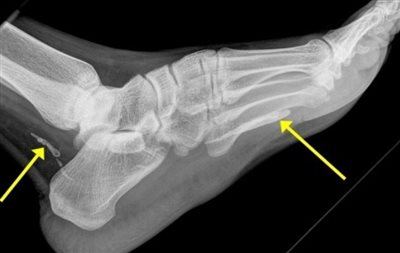

Τα υπολείμματα από το μήκους ενός μέτρου σκουλήκι φαίνονται καθαρά σε ακτινογραφία που έγινε στο νοσοκομείο St. Vincents του Σίδνεϊ.

Σύμφωνα με τον γιατρό Τζόναθαν Ντάρμπι, η ακτινογραφία έδειξε ότι δύο κομμάτια από το «σκουλήκι της Γουινέας» είχαν κουλουριαστεί στον αστράγαλο και την πατούσα του άνδρα.